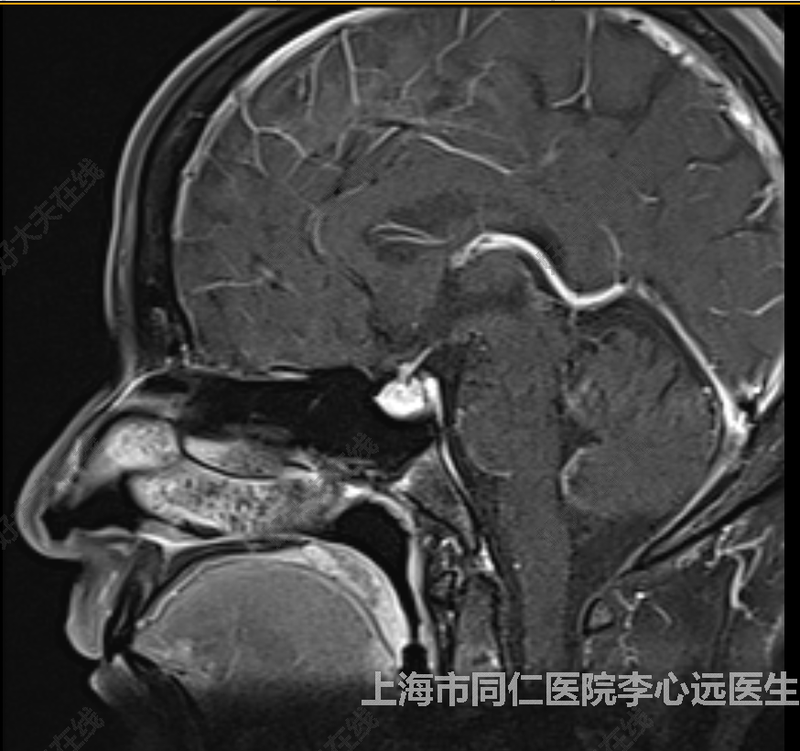

治療前 患者2008年無(wú)明顯誘因出現(xiàn)泌乳,分泌物為淡黃色透明液體,無(wú)疼痛,無(wú)視力下降,無(wú)頭痛頭暈,于醫(yī)院檢查發(fā)現(xiàn)垂體瘤,患者未行正規(guī)治療,規(guī)律隨訪。近自覺(jué)視力下降,于我院復(fù)查,垂體增強(qiáng)MR:垂體局部不對(duì)稱膨隆,高度約9mm, 右側(cè)見(jiàn)稍低信號(hào)灶,直徑約4mm,垂體微腺瘤可能,請(qǐng)結(jié)合臨床生化檢查?,F(xiàn)為進(jìn)一步治療,擬診“鞍區(qū)占位”收住入院。 治療后 治療后即刻 患者完善檢查,垂體增強(qiáng)磁共振示垂體左份占位,考慮垂體腺瘤可能。激素提示:泌乳素異常升高,是正常水平的8倍,泌乳是泌乳素異常增高引起,適合通過(guò)微創(chuàng)手術(shù)經(jīng)蝶竇(鼻腔)將腫瘤切除。經(jīng)蝶竇微創(chuàng)手術(shù),優(yōu)點(diǎn)是體表無(wú)手術(shù)疤痕,術(shù)后恢復(fù)快。病人接受微創(chuàng)手術(shù)。手術(shù)順利,術(shù)后泌乳素恢復(fù)正常,患者一周出院,無(wú)并發(fā)癥。